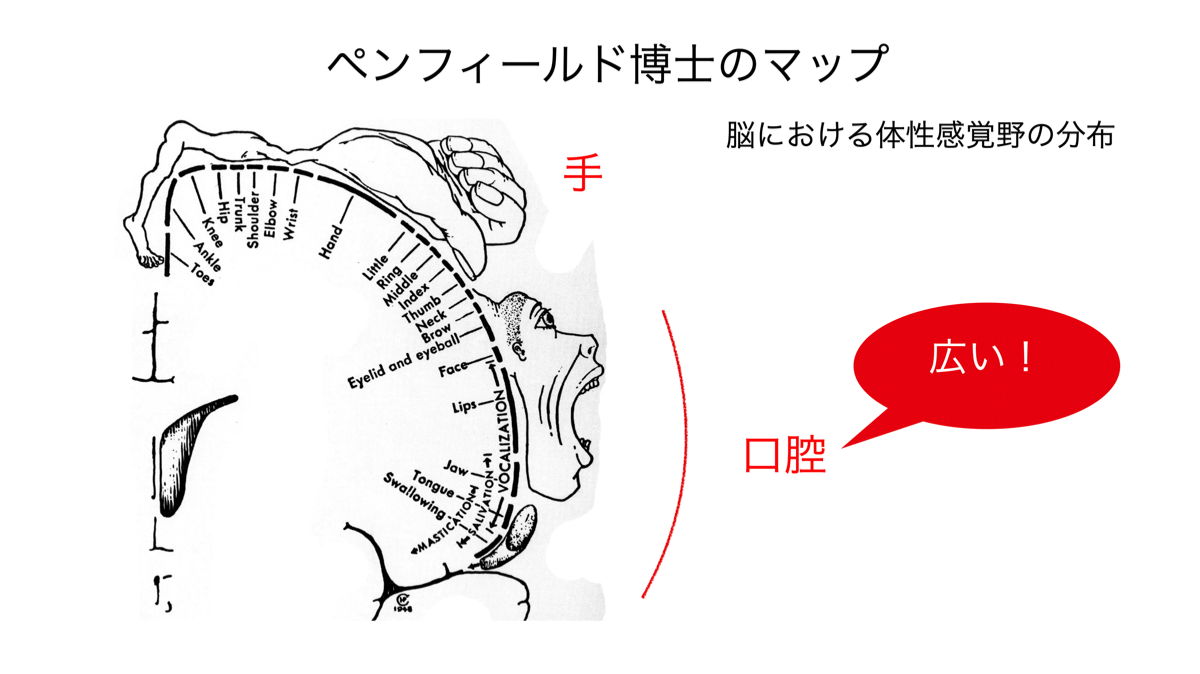

1950年にペンフィールド博士は、脳における体性感覚野の分布状況を明らかにしました。口と手の感覚が大半を占めていました。

認知症の予防で指遊びや手指を使うことは広く知られています。

同様に口腔の感覚を維持することも極めて大切です。

表情筋をしっかりと動かして顔の表情を作り楽しくおしゃべりをする。おいしい食事をしっかり咬んで飲み込む。毎日実践してこそ認知症予防です。

もし歯を失って義歯での治療を選択した場合には、感覚に優れる義歯が良いと考えられます。